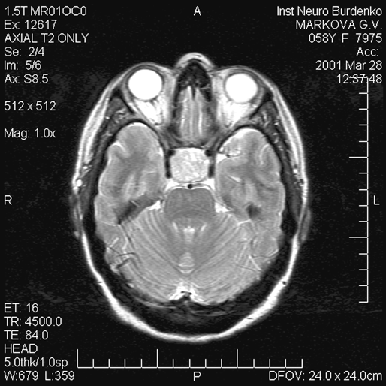

Диагностика опухоли гипофиза включает МРТ, исследование остроты и полей зрения и оценку эндокринологического статуса больного — как клиническую, так и исследование содержания гормонов (передней и задней долей гипофиза, щитовидных, половых, кортизола) в сыворотке крови. Большинство аденом характеризуется низким сигналом на Т1— и высоким — на Т2-взвешенных изображениях (рис. 2–4). Микроаденомы лучше визуализируются после внутривенного введения препарата гадолиния. КТ может иметь значение для уточнения характера костных изменений и размеров турецкого седла.

Рисунок 4. Аденома гипофиза средних размеров (МРТ, Т2-взвешенное изображение, аксиальная проекция)